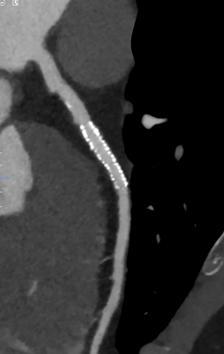

①DLを用いて設計された再構成技術AiCE

画像の信号成分とノイズ成分を高度に識別する再構成技術として当社が開発した、Advanced intelligent Clear-IQ Engine (AiCE)*がある。これは、Deep Convolutional Neural Network (DCNN)を用いて信号成分とノイズ成分を識別し、CTの画像再構成に適用したもので、ノイズ成分が多くなりやすいエックス線高吸収領域や低線量条件下でもノイズが抑えられた画質が得られる。図6は、腎機能が低下した患者の造影撮影画像であるが、腎臓への負荷軽減のため造影剤使用量を少量(170mgI/lg:30ml)とし、コントラストを高めることと被ばくを低減するために低管電圧(80kVp)でCT撮影し、AiCEを用いて再構成した画像である。低管電圧であるため、被写体に照射されるエックス線量は抑えられるが、信号成分となる被写体を透過してきたエックス線量も減少するため、ノイズが多くなりやすい。AiCEでは信号成分とノイズ成分を識別するためノイズの影響を抑えた画像が再構成されている。

- 左:cMPR(curved Multiplanar Reconstruction)法処理画像

- 右:ボリュームレンダリング法処理画像